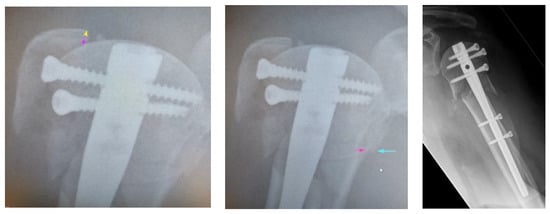

2.4. Radiographic Evaluation

| Anatomical Parameter | Anatomical | Acceptable | Malreduction |

|---|---|---|---|

| Head-Shaft-Displacement | Anatomical | <5 mm | >5 mm |

| Head-Shaft-Alignment | Normal, 120–150° | Minor varus, <120–100° | Valgus, >150°, <110° |

| Cranialization of the Greater Tuberosity | Anatomical | <5 mm | >5 mm |